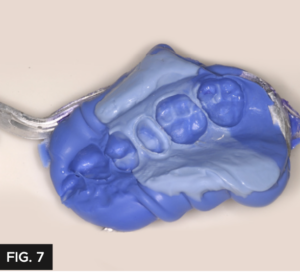

This technique provides great detail and has a perfect flow to allow the impression material to encompass the prep without the InFlex tray material showing through. (FIG. 6) Affinity InFlex has a higher durometer hardness to support the Quad-Tray Xtreme’s sideless wall design and will not distort during pour up. (FIG. 7)